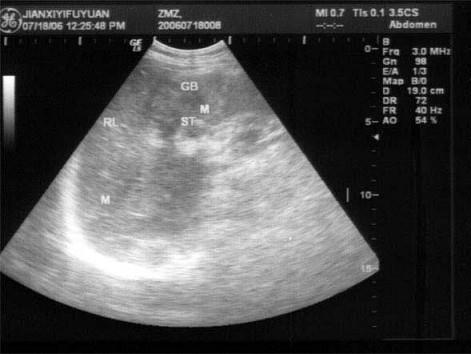

问题 患者男46岁,既往有胆囊结石病史,上腹部疼痛不适年余,加重1个月,皮肤、巩膜轻度黄染,B超检查如图所示,根据超声声像图,诊断为?(?)

选项 A.胆囊结石并胆囊炎,肝血管瘤 B.胆囊结石并胆汁淤积,肝血管瘤 C.胆囊结石并胆囊癌,肝转移性癌 D.胆囊结石并肝癌 E.胆囊结石并胆息肉,肝转移性癌

答案 C